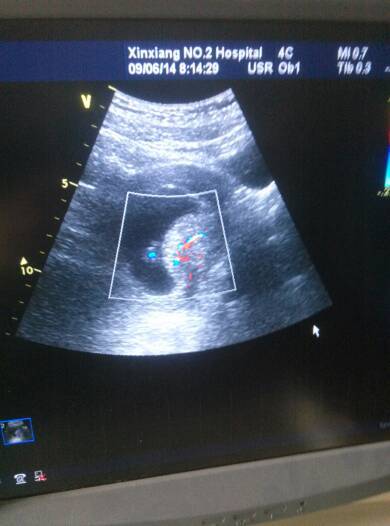

66天的bc有胎心胎芽 请问有血流是什么意思? 66天的bc有胎心胎芽 请问有血流是什么意思? 点击展开 て°傻了吧唧、 2014-06-17 15:03 为您推荐: 其他回答 根据B超报告考虑胎儿发育正常,建议卧床休息、孕酮低者黄体酮补充。 lijie020826 2014-06-17 15:17 如果有出血要注意,有可能是先兆性流产,宝妈要注意休息 林瑾萱 2014-06-17 15:08 相关问题 五十天bc能看出来胎心胎芽吗? 急 我怀孕八个多月了 B超显示 双顶径86 股骨长66 羊水最深50 胎心搏动140 胎盘厚26 PW 脐动脉血流S/D2 3 怀孕40天了,做b超为什么说不见血流信号啊,什么意思啊